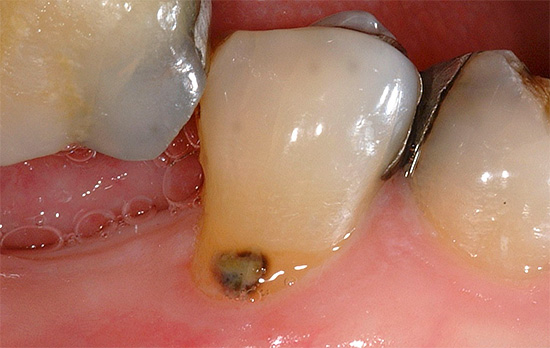

Se la malattia si sviluppa nella regione cervicale del dente, cioè in aree vicine alla gengiva, allora in questo caso stiamo parlando di carie cervicale. Una tale patologia ha anche un aspetto caratteristico: alla base, il dente sembra essere minato, a volte lungo l'intero perimetro, mentre la parte superiore della corona rimane spesso generalmente intatta.

Le fotografie seguenti mostrano alcuni esempi di carie cervicale: